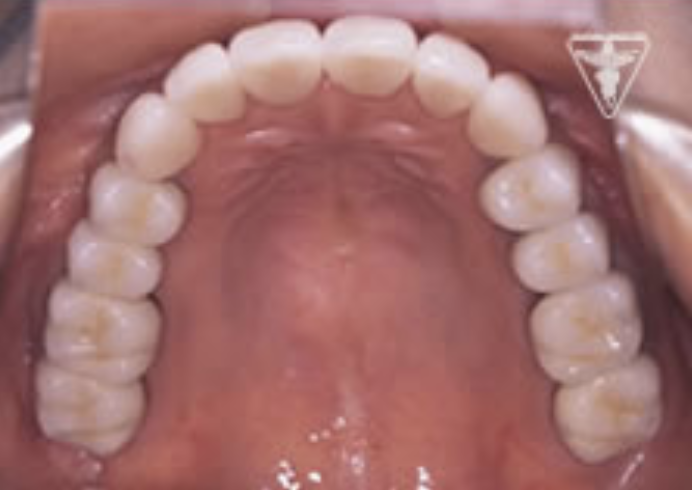

治療後

顎のずれを改善し、上下のかみ合わせの関係を理想的にして筋肉や関節の緊張が取れ、穏やかな表情に変られました。「良く噛めるようになった。」と評価をいただきました。

リコールに真面目に通われており、感謝しております。

やり直しがないように、しっかり管理させていただきます。